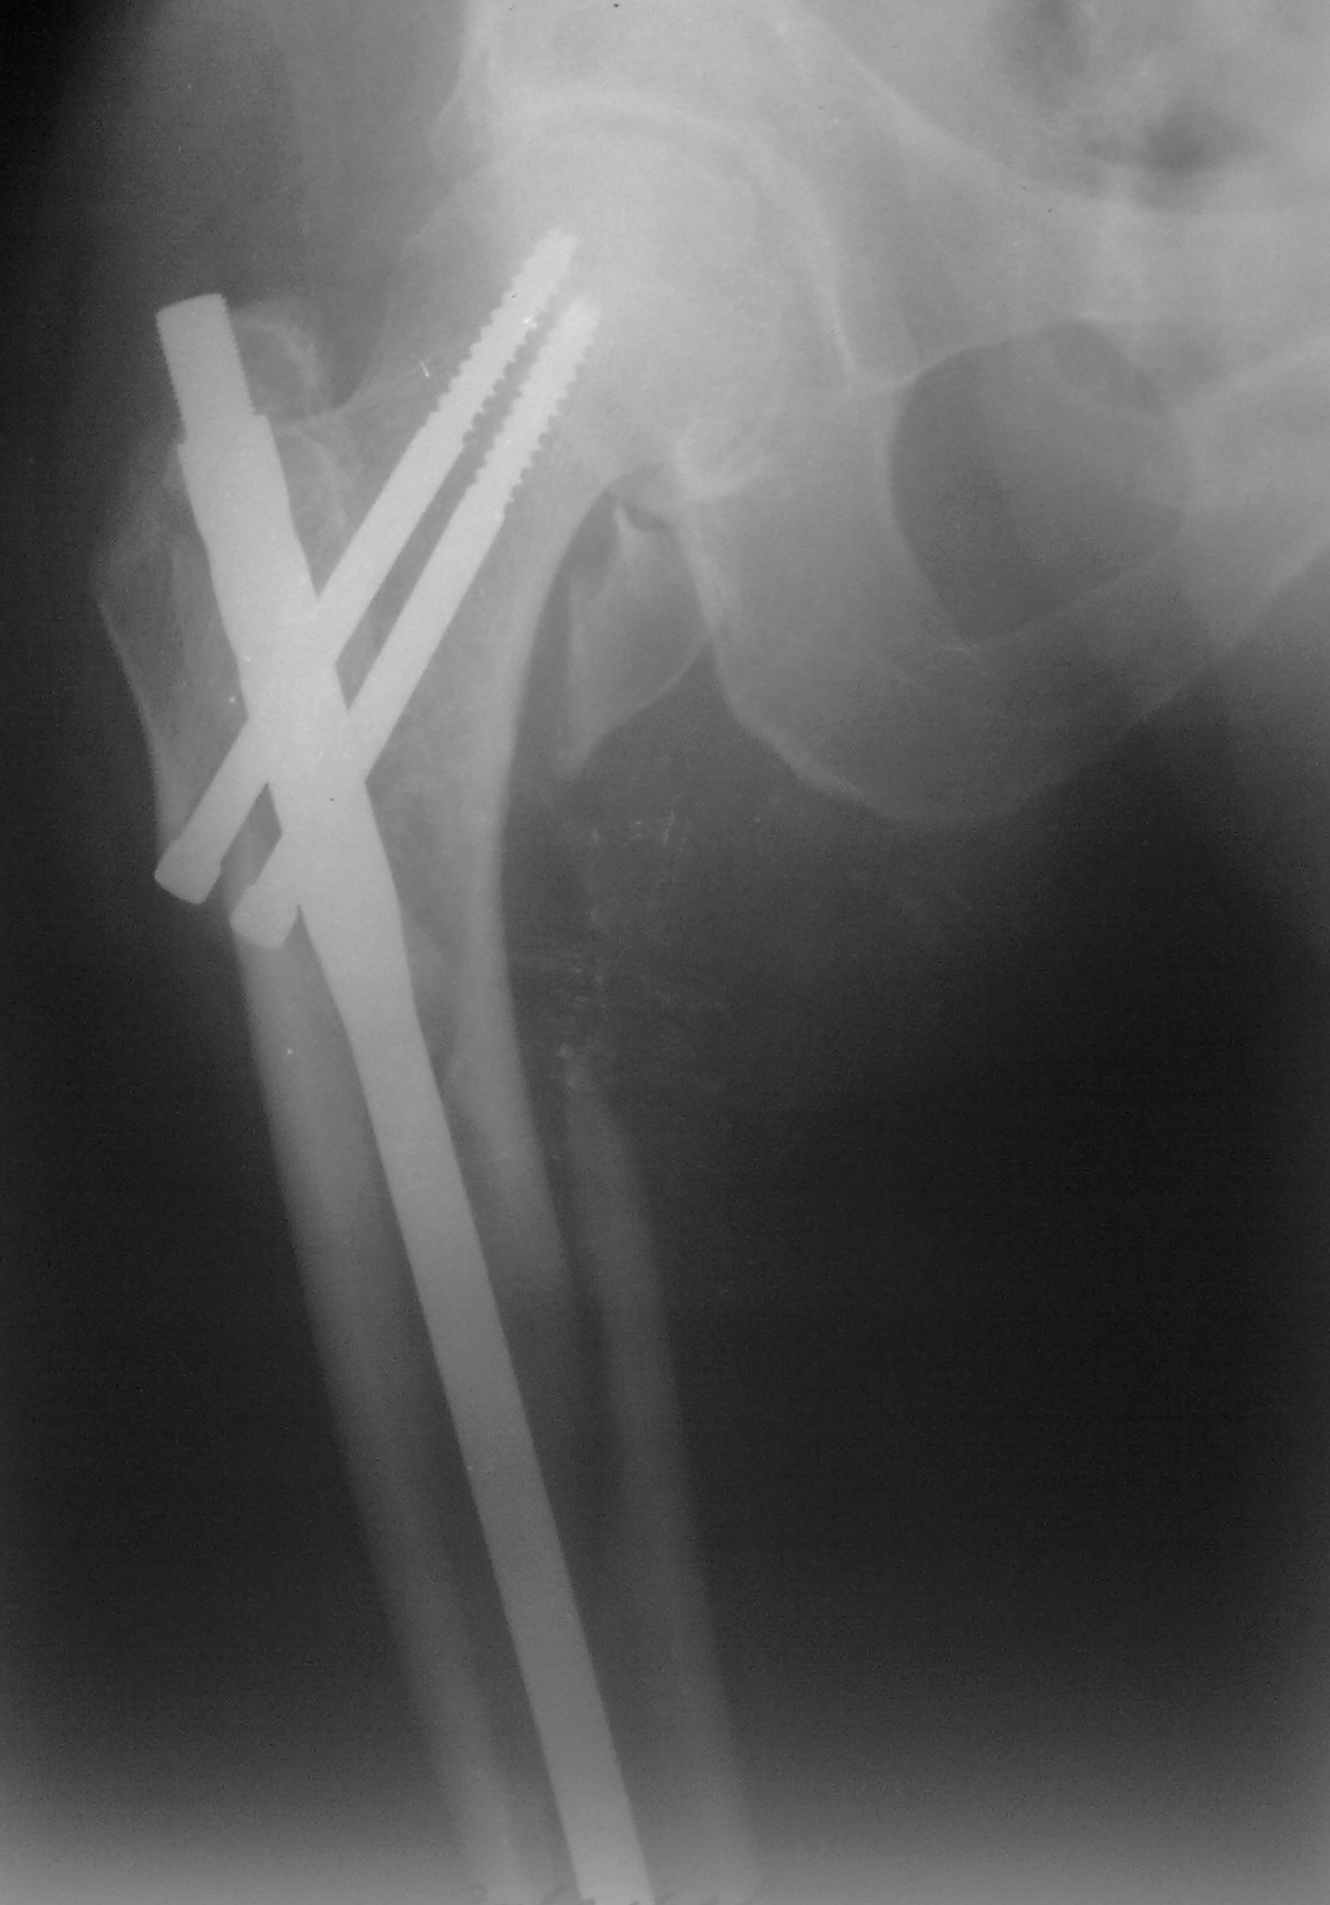

Пациент 83 года. Реконструктивный бедренный стержень Chm